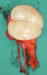

Renal oncocytoma with the characteristic central stellate scar of the neoplasm (Courtesy Dr. V. Penopoulos)